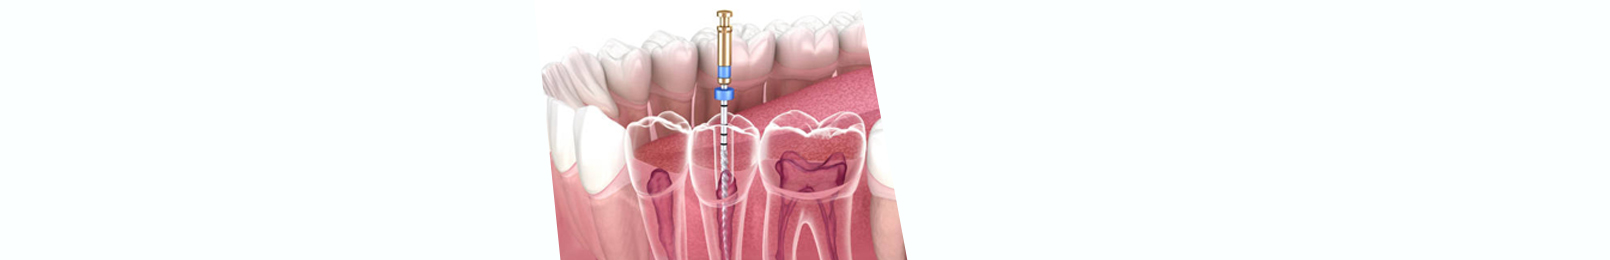

What is Scaling?

Scaling involves the removal of plaque and tartar‍ from the surface of the teeth and below the ​gum line. While brushing ‌and flossing can ‍remove many of the plaque deposits, it can’t remove tartar. Tartar is‍ hardened plaque and must ​be scraped away ‌by a ‍dentist using specialized tools.